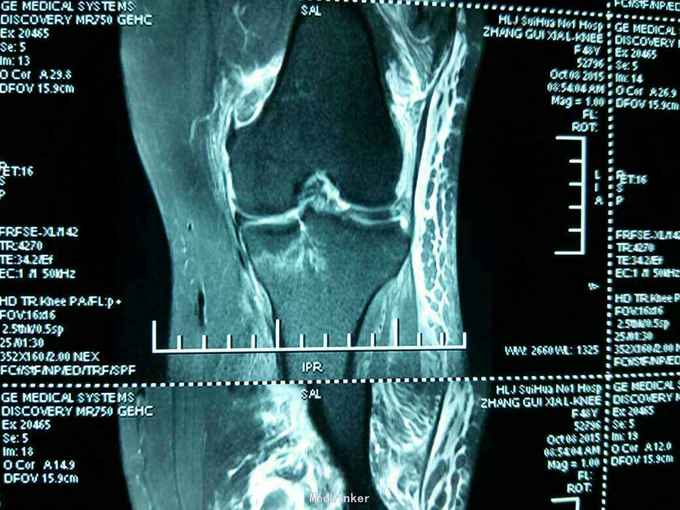

患者女性,48岁。因摔伤左膝关节,肿胀,畸形,活动受限二小时来诊。病人于二小时前滑倒摔伤,当即左膝关节肿胀畸形,局部肿胀,不敢下地行走。门诊拍片示:左膝关节胫骨平台塌陷骨折。以:左胫骨平台塌陷骨折收入院。

左膝关节局部肿胀,局部压痛。浮髌试验阳性。膝关节屈伸活动受限。不能下地行走。侧方应力实验阴性。抽屉实验阴性。拍片示:左胫骨平台骨折。核磁共振示:左胫骨平台塌陷骨折。局部骨质塌陷约1cm